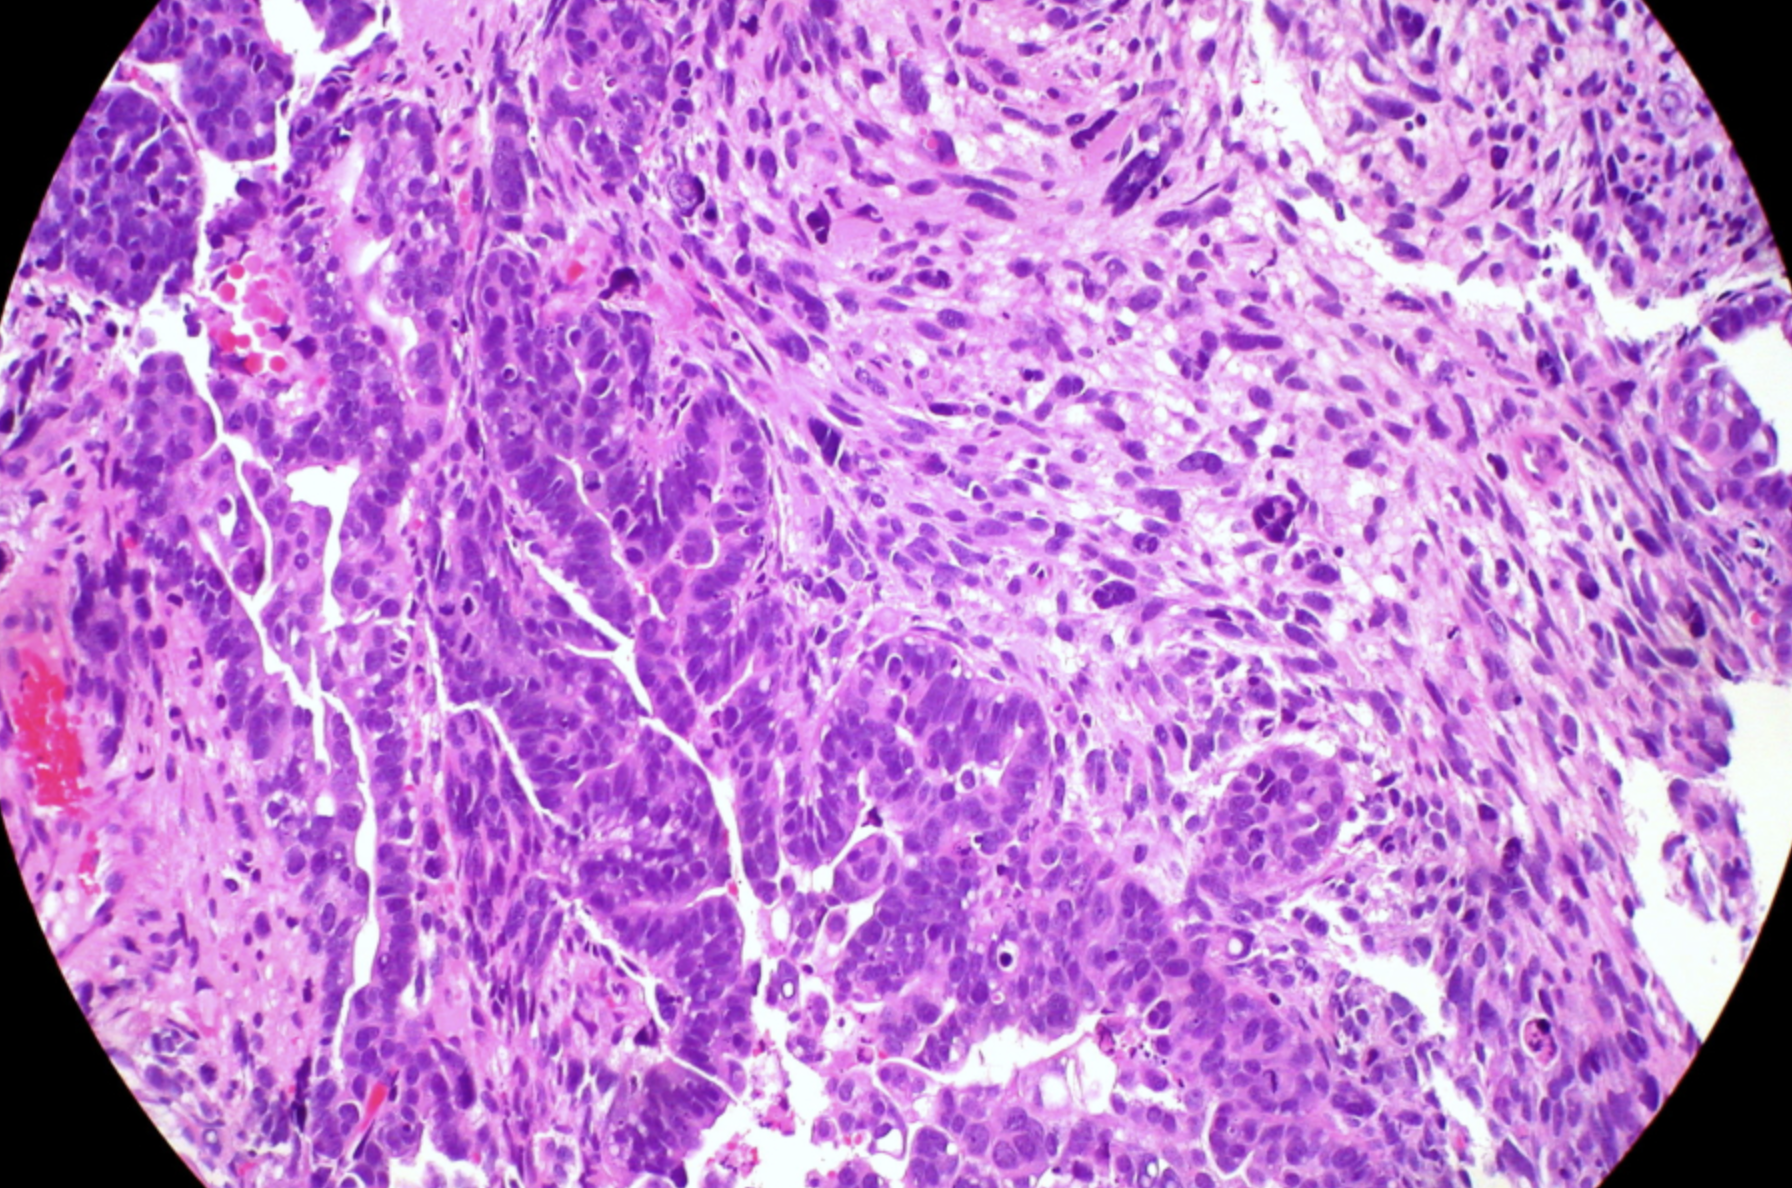

Carcinosarcoma d'endometri / Foto: Ed Uthman (CC BY 4.0)